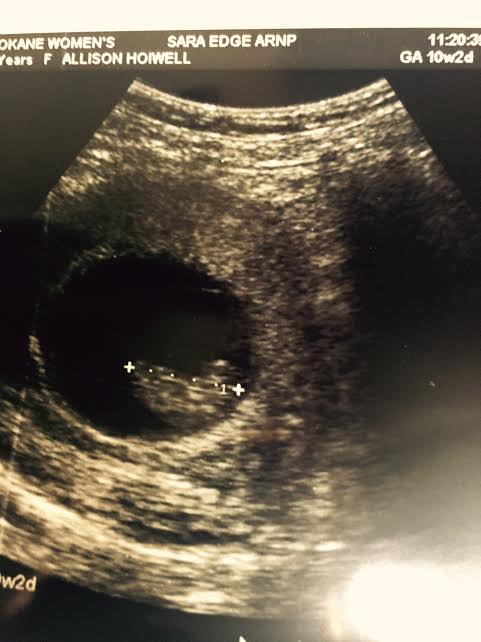

Well, it has been a while. Not that life has been that boring, but it has been busy. On top of the busyness, my days have been cut short. Well, my hours of productivity that is. Yes, even during my 12th pregnancy, I’m still exhausted and sick. Oh, did you catch that? I am 10 1/2 weeks pregnant! Yay!

The Lord’s ways are truly not our ways, are they? Now, I have had 2 miscarriages past this point, but I decided 5 weeks ago I would officially announce this baby when I had my 10 week ultrasound. My due date is March 13, 2016- I will still be 41 then.

It still looks like a jelly bean, but moves around much better than one!